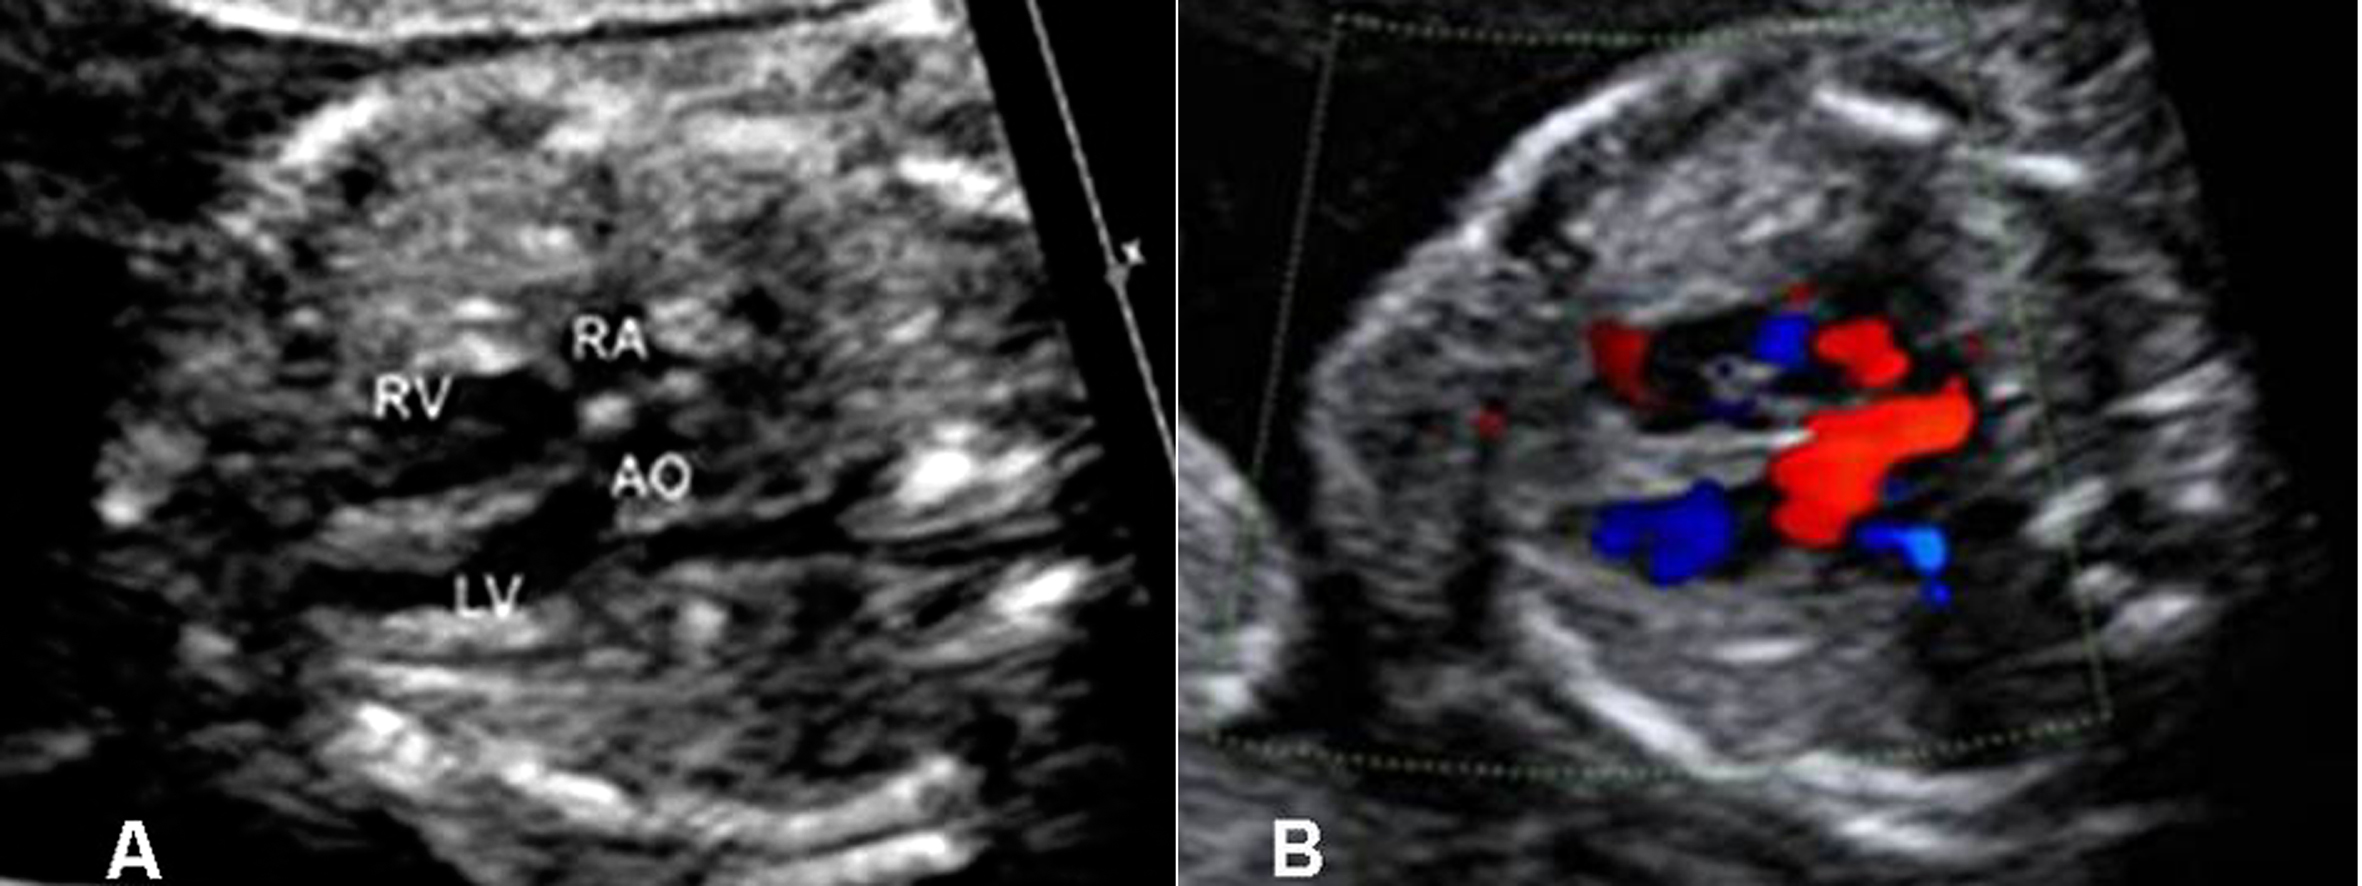

CDFI检查胎儿二尖瓣口(MVO)显示为稍细的红色血流,三尖瓣口(TVO)的红色血流较MVO稍粗;TVO的血流速度较MVO快。在瓣口远端取样,可以获得MVO和TVO的血流频谱,舒张期显示E峰和A峰。E峰由心室舒张的快速充盈血流形成,A峰由缓慢充盈期心房收缩、血流加速而形成,双峰特点在MVO显示的更为明显(图1)。瓣口血流速度随着孕龄的增加而增加,但38孕周后血流速度有所下降。

图1 MVO(A)和TVO(B)流速曲线,E峰<A峰

胎儿心室充盈的最大血流速度出现在心房射血期,由此导致MVO和TVO显示E峰小于A峰,提示心房收缩在胎儿心室充盈中起了重要作用;随着孕周增加E/A比例增大,说明心室舒张能力逐渐增加。出生24h后E/A即可升至1.17。TVO流速>MVO流速,显示胎儿循环为右心室(RV)优势;这种右室优势在早孕期即开始,直到在孕晚期才逐渐转为左室优势。